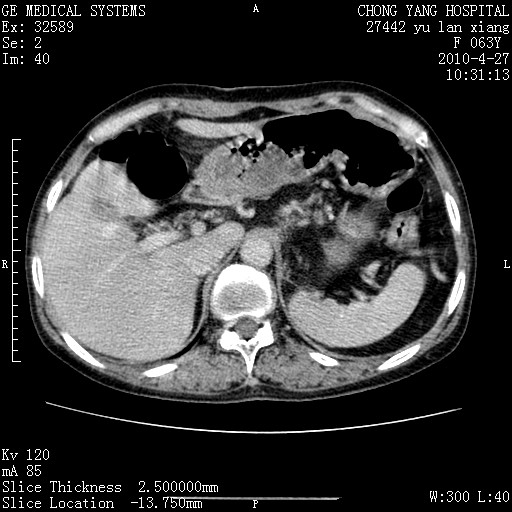

标题: CT26066:F63Y 上腹正中压痛半月,CA199:7400u/ml,MR示胰腺炎伴 [打印本页]

胰腺癌侵犯腹腔动脉干-分支、胃壁、左侧膈肌伴胰周及腹膜后淋巴结转移、胆囊切除术后。

胰腺癌侵犯腹腔动脉干-分支、胃壁、左侧膈肌伴胰周及腹膜后淋巴结转移、胆囊未显影。